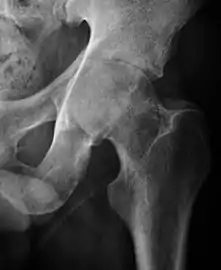

Plain radiography allows us to categorize the hip as normal or dysplastic or with impingement signs (pincer, cam, or a combination of both). Besides these, pathologic processes like osteoarthritis, inflammatory diseases, infection, or tumors can also be identified (Figure 1).[1]

Figure 1.

Radiography in normal hip

X-ray in pincer impingement type of hip dysplasia

X-ray of cam

Hip in osteoarthritis

Septic arthritis

In adults, one of the main indications for radiographs is the detection of osteoarthritic changes (Figure 1(e)). Nevertheless, radiographs usually detect advanced osteoarthritis that can be graded according to the Tönnis classifications. The grading system ranges from 0 to 3, where 0 shows no sign of osteoarthritis. Intermediate grade 1 shows mild sclerosis of the head and acetabulum, slight joint space narrowing, and marginal osteophyte lipping. Grade 2 presents with small cysts in the femoral head or acetabulum, moderate joint space narrowing, and moderate loss of sphericity of the femoral head. Grade 3 is the severest form of osteoarthritis, which manifests as severe narrowing of the joint space, large subchondral cyst with productive bone changes that may lead to deformity of the bone components of the joint, while secondary osteoarthritis due to calcium pyrophosphate deposition can be diagnosed when calcification of hyaline cartilage and fibrocartilage is detected.[1]

There are other pathological conditions that can affect the hip joint and radiographs help to make the appropriate diagnosis. Acute bacterial septic arthritis can be diagnosed by radiographs when a fast regional osteoporosis and destructive monoarticular process develops (Figure 1(f)). In case of tuberculous or brucella arthritis it is manifested as a slow progressive process, and diagnosis may be delayed.[1]